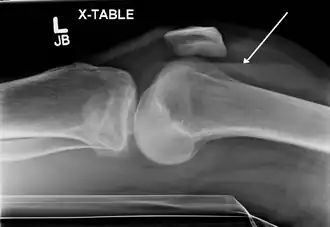

Description de cette image, également commentée ci-après

Lipohémarthrose (présence de sang et de graisse dans l'épanchement hémorragique) est une fracture articulaire du plateau tibial interne. La flèche indique un niveau de liquide entre le composant gras supérieur et le composant sanguin inférieur.